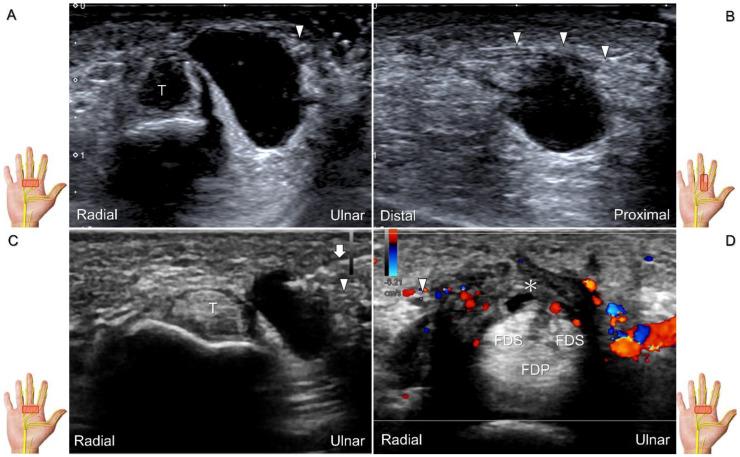

超声已成为一种极具价值的工具,用于腕部区域周围神经病变的成像,特别是对于诸如腕管综合征和尺神经管综合征等常见病症。大量研究表明,神经在卡压部位近端肿胀、边界不清和平扁是神经卡压的特征。然而,关于腕部和手部的小神经或终末神经的信息却很匮乏。本文旨在通过全面概述这些神经卡压的扫描技术、病理学和引导注射方法来填补这一知识空白。本综述详细阐述了正中神经(主干、掌皮支和返支)、尺神经(主干、浅支、深支、掌尺皮支和背尺皮支)、桡浅神经、骨间后神经、掌总/指固有神经和背总/指固有神经。一系列超声图像用于详细说明这些技术。最后,超声检查结果补充了电诊断研究,有助于更好地理解整个临床情况,而超声引导下的干预措施对于治疗相关神经病变是安全有效的。